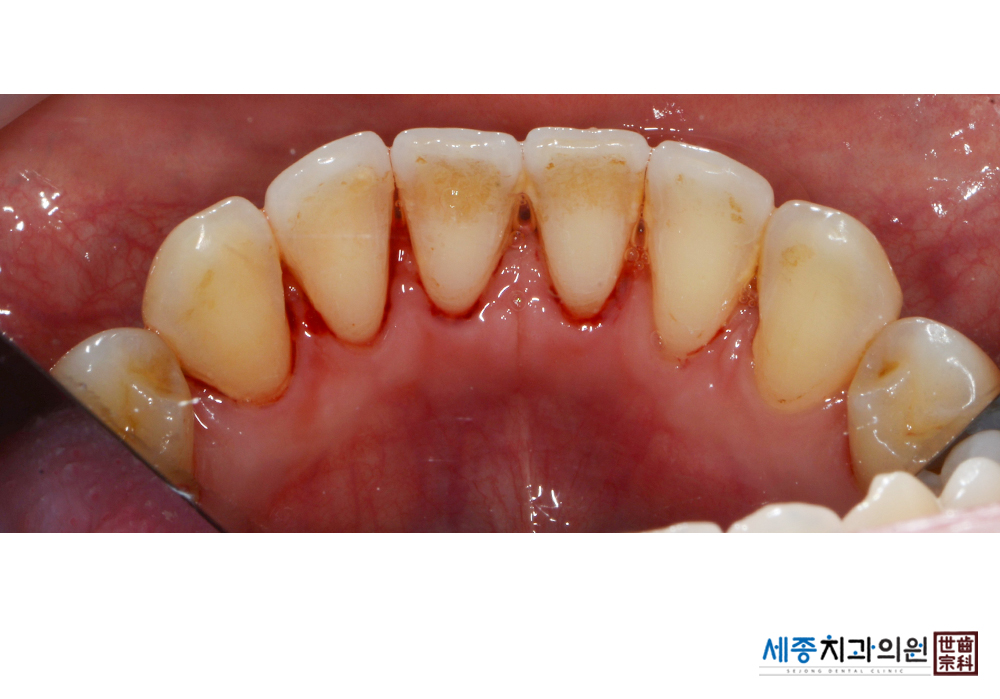

[스케일링] 치주질환 예방 스케일링 치료

치료전 : 2019-01-28

가글마취&저주파 스켈러를 사용한 스케일링